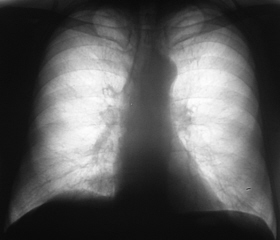

Иллюстрация 1. Флюорограмма в прямой стандартной проекции. При анализе полученного изображения было констатировано усиление и обогащение легочного рисунка справа медио - базально. Было отмечено некоторое уплотнение тени правого корня в области тела. В остальном отмечены изменения возрастного характера.